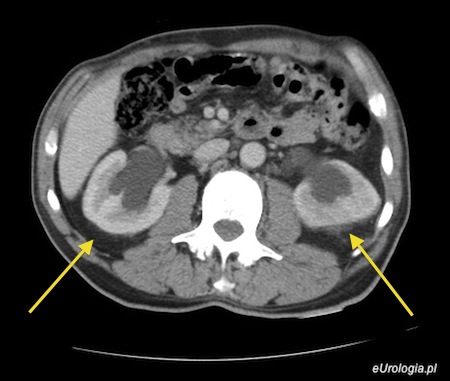

Powiększający się gruczolak stercza powoduje unoszenie trójkąta pęcherza moczowego co skutkuje uciskiem śródściennych odcinków moczowodów. Ucisk na moczowody przyczynia się do powstania utrudnionego odpływu moczu z nerek co często objawia się poszerzeniem UKM w badaniu ultrasosnograficznym. Czasami u pacjentów z zaawansowanym przerostem gruczołu krokowego obserwuje się odpływy pęcherzowo - moczowodowe objawiające się cofaniem się moczu z pęcherza do moczowodów i układów zbiorczych nerek. Utrzymujący się odpływ pecherzowo moczowodowy i większone ciśnienie w układach zbiorczych nerek prowadzą z czasem do powstania pozanerkowej niewydolności nerek.

Fot. Przerost gruczołu krokowego z wtórnym wodonerczem obustronnym - skan z tomografii komputerowej.